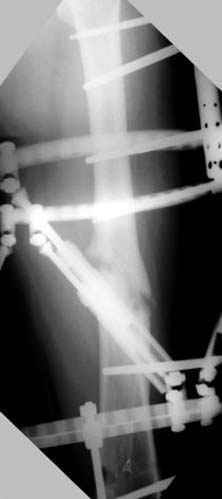

Отправитель: Djoldas Kuldjanov 23 Ноябрь 2004, 18:21

пластическая модель; и коррекция бедра аппаратом Илизарова.

Имею другие снимки тоже, получится как отчет о моей работе.

Почему не замена гвоздя с рассверливанием, а аппарат?

Узкий к-м канал - тонкий гвоздь- усталостный перелом дистальных винтов - развитие нестабильности и как ее результат остеолиз вокруг гвоздя - деформация анатомической оси бедра. Похоже, что я понял почему аппарат, а не новый гвоздь:-)

ЕТ - Изначально костно-мозговой канал бедра был узкий, дальнейшее его рассверливание ещё больше скомпрометирует прочность бедра( латеральный кортекс дистального отломка уже истончен), приведет к дефекту наружной стенки - хотя это только мои догадки - хотелось бы знать мнение Джолдаса о выбранной тактике.